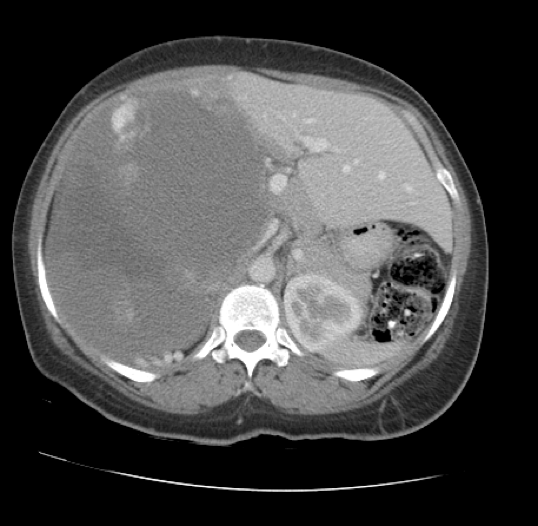

Later that year, CT of the abdomen and pelvis with intravenous (IV) contrast showed a large heterogeneous peripherally and nodular enhancing mass (17.4 × 13.7 × 16.8 cm) occupying most of the right hepatic lobe, causing hepatic enlargement and mass effect on the adjacent abdominal viscera (Figure 2).

Figure 2. Transverse CT scan showing a mass occupying most of the right lobe of the liver.